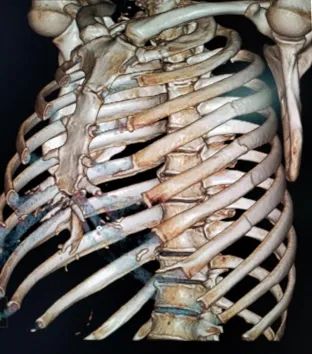

▲40排40层CT检查

骨折CT表现